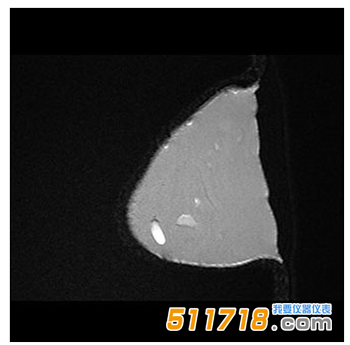

CIRS 073多模式乳房活檢和超聲波訓練模體 MR T2 FSE